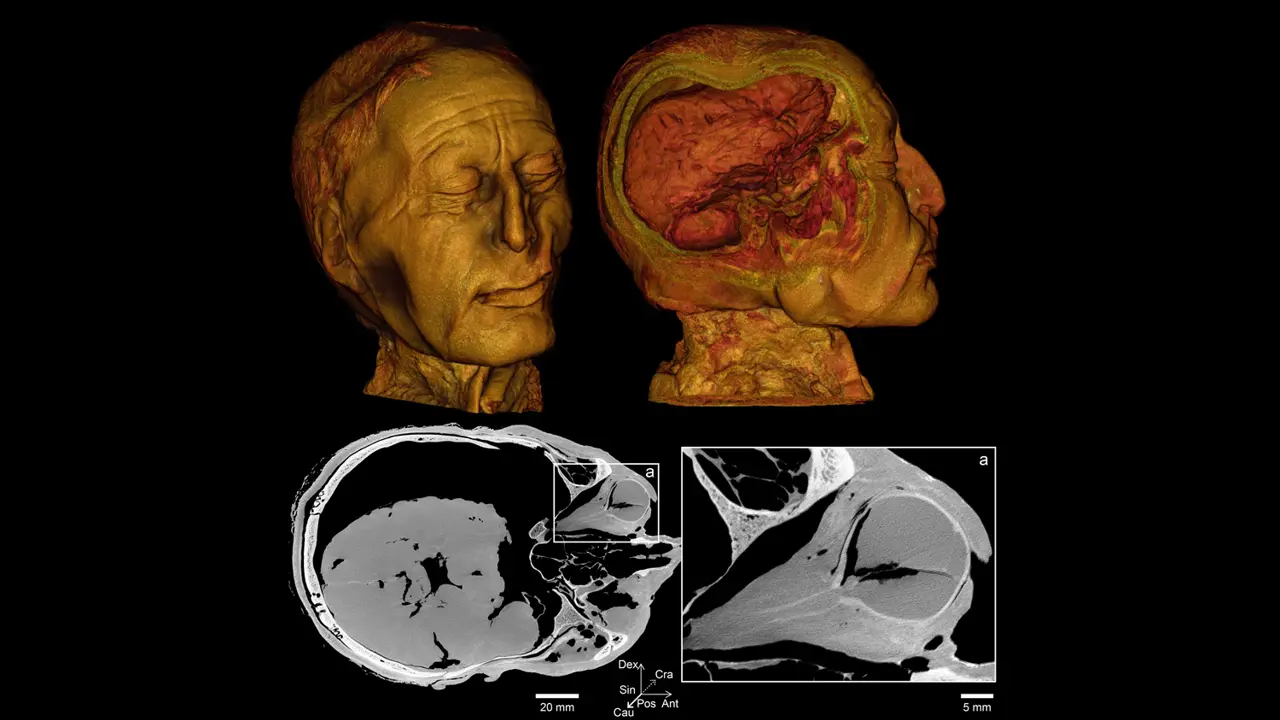

Nu har danske forskere fra Aarhus Universitet og Museum Silkeborg igen haft ham under videnskabelig granskning, denne gang med brug af både en klinisk CT-scanner og universitetets nye mikro-CT-scanner, som kan tage billeder med meget stor detaljeringsgrad. Helt præcist er de nye billeders opløsning 422 gange bedre end opløsningen i 2002.

Den nye mikro-CT-scanner adskiller sig fra universitetets andre scannere ved, at den både kan scanne små prøver ved ultrahøj opløsning og producere billeder af store genstande – så som et helt hoved fra et oldtidsmenneske. Igen er det da også hovedet, der har været genstand for undersøgelse, særlig med fokus på tænderne, halsen og øjnene.

Intakt synsnerve i det ene øjne

Scanningerne har blandt andet afsløret, at Tollundmandens ene øje er fuldstændig intakt med form og synsnerver, mens hans andet øje er punkteret. De har også givet hidtil uset detaljerede billeder af hans tænder, som blandt andet kan fortælle noget om ernæringstilstand og eventuelle sygdomme, han led af.

Tollundmandens højre øje og hjerne er velbevaret. Øjet indeholder stadig linse og en intakt synsnerve. Foto: Aarhus Universitet og Museum Silkeborg

Fordi Tollundmanden har ligget i en syrlig mose i over 2000 år, er meget af hans knoglemineral udvasket. Det betyder, at kontrasten mellem knogler og det bløde væv er mindre end normalt.

Med en mikro-CT-scanner kan forskerne imidlertid opnå bedre kontrast på de forskellige væv og se mange detaljer.